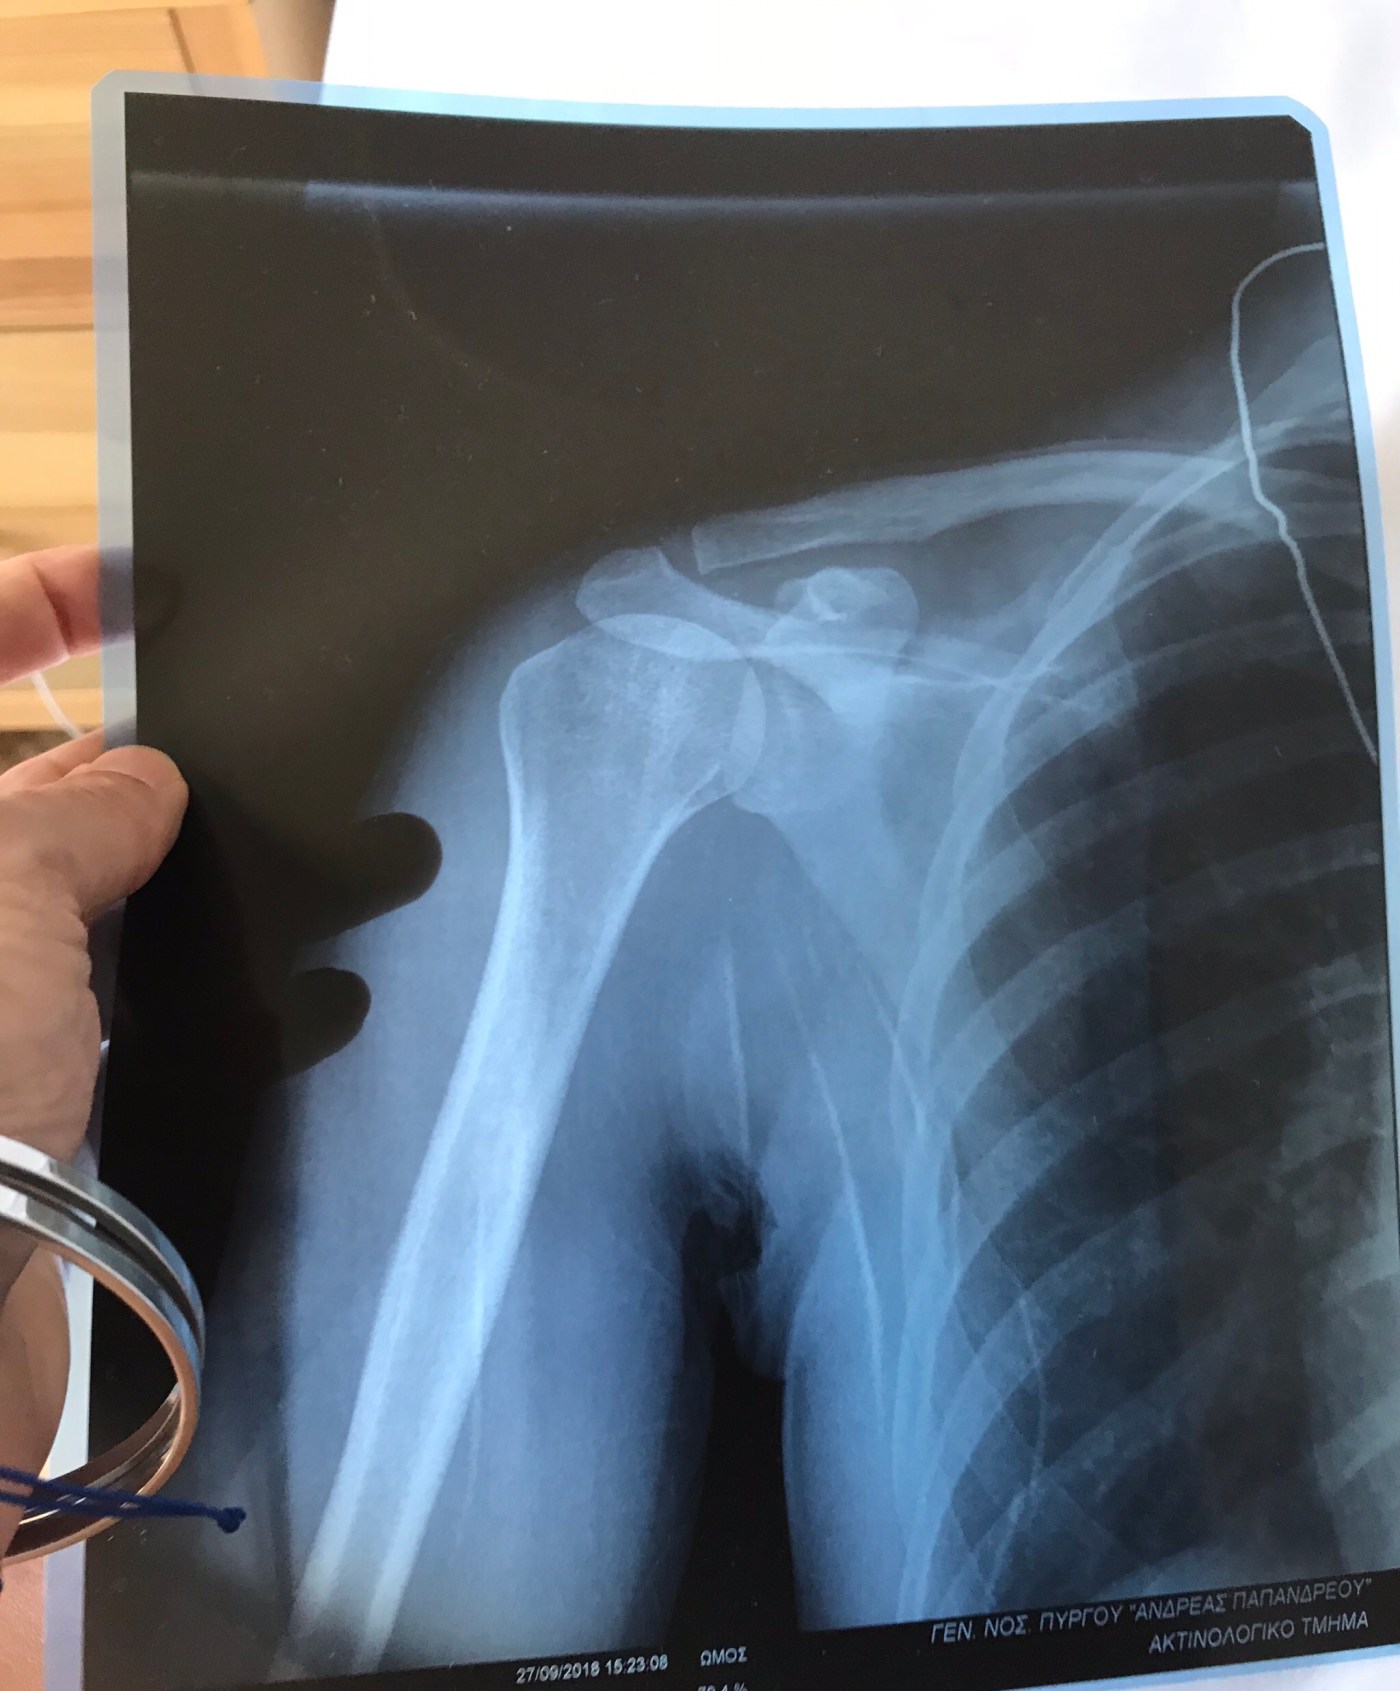

And then another significant change occurred that made the effect of weather variations seem merely an interesting triviality and certainly nothing to get attached to or bothered about. So what happened, what changed? Just a fall, just a silly little trip. I slid on a dusty patch on an archaeological site, falling up some steps and landing heavily on my shoulder. Then the rest of the day spent visiting two health centres and a hospital, getting an x-ray, and waiting, waiting, waiting… The bafflement of negotiating Greek health care, trying to muster the words to explain what happened, whimpering with pain as the doctor handled me brusquely through range of movement tests, breathing into the pain and the fear of a dislocation or fracture, finally sobbing with relief at the diagnosis of only contusions to the supraspinatus. Told to rest and revisit in 5 days — at which point I’ll be back in UK and able to chat more freely with my regular GP or physio.

Now 24 hours later I’m filled with gratitude to the site guards who drove me to the first health centre, Hubby who then got me to the hospital and home, the kindly family visitors at the hospital who walked me between departments because I didn’t know the way and couldn’t understand the signs. Grateful, bizarrely, to years of reading Homer in the original Greek, which gave me enough vocabulary of injured body parts on the ancient battlefield to stop the modern doctor x-raying my elbow rather than my shoulder! šŸ™‚